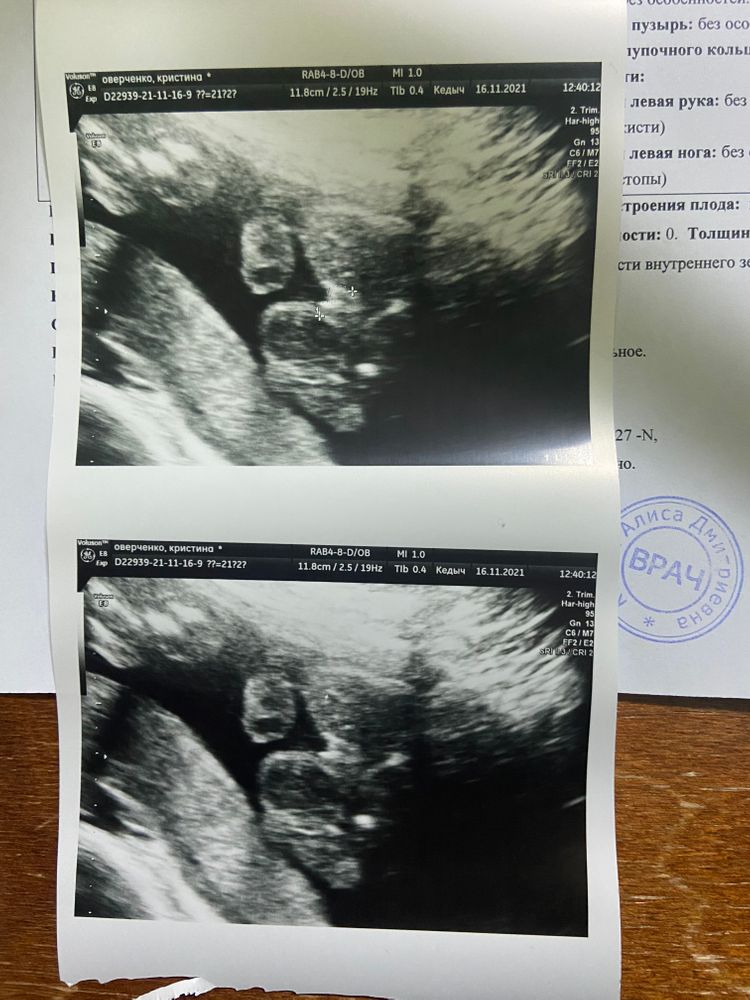

И так, второй скрининг пройден..что же происходило до него? в 12 недель предположили девочку, в 21 неделю подтвердили, заболела ковидом на 17 неделе, состояние было ужасное, сейчас более менее восстанавливаюсь, на 19 недели начала ощущать первые шевеления, начал резко расти живот, побаливать поясница, а так же я поняла что такое тонус. Далее перейдем ко второму скринингу, ох и намучалась я сегодня у кабинета узи. Первый раз зашла сказали лежит неудачно и нужно идти кушать сладкое (пошла съела мафин шоколадный с чаем), второй раз пошла все померили кроме носа, так как не поворачивалась малышка, сказали постоять (простите раком), но и это не помогло, отправили пить ношпу и ходить, на третий раз о чудо все замерили и все хорошо. На второй скрининг мужа не пустили, скорее всего из за ковида, а я его вызволила с работы, конечно хотела чтобы и он посмотрел. Кстати на 6-7 недели выкладывала пост с узи и спрашивала девчонок о методе Рамзи по определению пола и все как один говорили что будет мальчик, только 1-2 человека сказали что девочка и они оказались правы) Прикрепляю фото на память 🥰